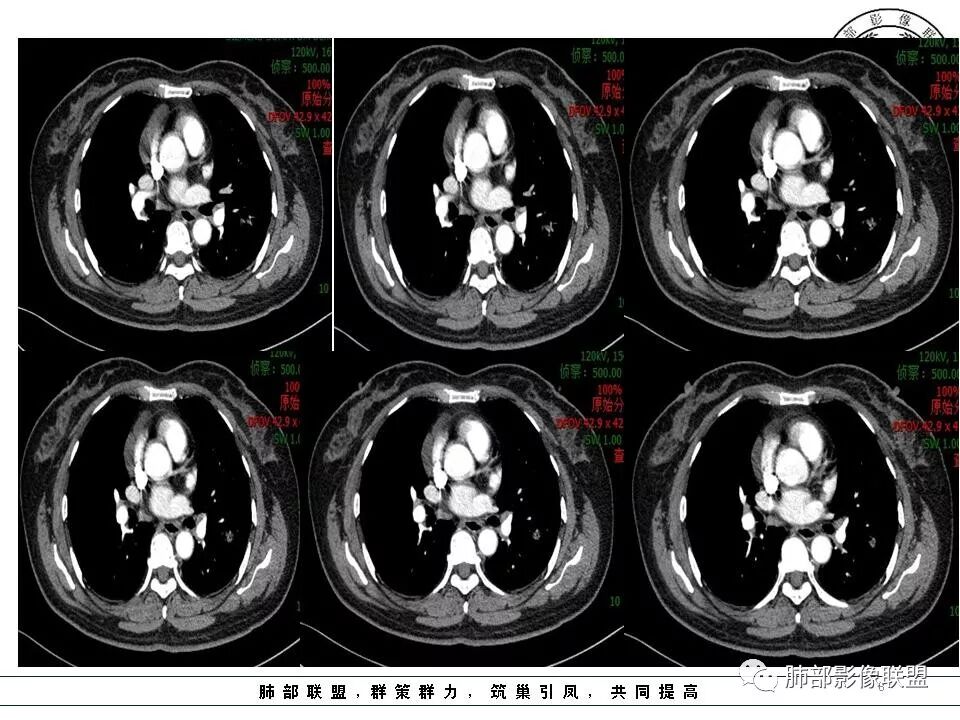

徐婕:同意恶性腺癌可能岁月:女,56;空泡,分叶毛刺,牵拉线,胸膜凹陷征,有强化,浸润性腺癌。THINKER:左舌见结节,膨胀为主,部分收缩,分叶丶短丶硬毛刺,牵拉斜裂,有小空泡,支气管穿行,有强化,常规腺癌丽:左肺上叶近胸膜下结节,胸膜牵拉,边缘膨隆,并可见深分叶及毛刺,内有空泡,增强后可见强化,倾向腺癌淘时光:混合磨玻璃结节,实性部分较多,内见支气管穿行,腺癌首先考虑了…☀:左肺上叶结节影,实性,边缘分叶征,其内可见空泡,部分膨胀生长,局部叶间裂牵拉上移,叶间裂光滑增厚,首先考虑肿瘤黄棘:左肺上叶结节,边缘彭隆, 周围磨玻璃影边界清,内部可见扩张支气管,叶间胸膜牵拉,考虑腺癌心灵鸡汤:左肺上叶舌段近斜裂处混合性结节,以实性成分为主,有分叶、毛刺,牵拉邻近叶间、脏层胸膜,增强有强化,影像学上看偏恶性,分类LU-RADS 4C类,MIA浸润性腺癌可能,鉴别肉芽肿性病变、隐球菌,请老师指点!THINKER:这个如果是腺癌,应该是IAC了,过MIA了,个人看法,罗老师一切∮随缘:左肺叶裂胸膜下结节,边缘收缩弱,周围有GGO,边界清楚,形态欠规则,其内似有支气管穿行,增强扫描轻度均匀强化,考虑1肉芽肿性病变(隐球,炎性假瘤)2:浸润性腺癌Clover:考虑腺癌,实性为主混合有少许边界清晰ggo,边缘膨隆,其内支气管气象不规则,有收缩力。Coke with ice:还有一个疑问请教一下:这个是混合磨玻璃结节还是实性结节?个人倾向于后者。心灵鸡汤:有部分磨玻璃Coke with ice:实性结节周围GGO初学者:实性,周围有毛玻璃晨:有浅分叶,有毛刺,有叶间裂牵拉,内有囊泡,考虑腺癌。初学者:稍等,我等会开电脑看,但是感觉和你们一样,感觉是一个典型病例来着Coke with ice:这个人我也倾向于腺癌。但是诊断腺癌还有一个比较疑惑的地方,肺窗病变密度显示比较实,但是纵隔窗病灶范围明显比肺窗小,腺癌可以解释的通吗?张小兵:混合磨玻璃结节,内见支气管穿行,分叶,胸膜牵拉从凹陷处进入,腺癌首先考虑小微:

是积液还是囊肿?Coke with ice:我倾向于囊肿初学者:心包隐窝?主要没有连续图

这些好像也大,会不会是肿大淋巴结